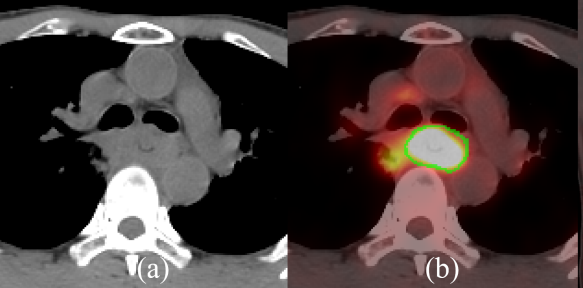

與CT相比,PET/CT可更為準確地勾畫食管癌原發腫瘤灶(綠線為真實腫瘤邊界)[2]